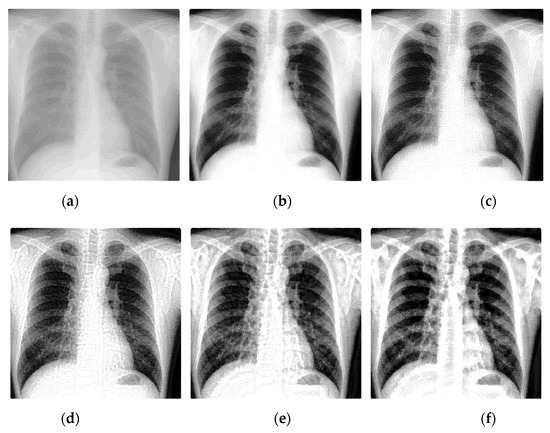

To demonstrate the effectiveness of the algorithm in this paper, experiments were carried out on five X-ray images, as is shown in Figure 9, in which (1) and (2) are medical images mentioned before, (3) and (5) are industrial images with a size of 2048 × 2048, and (4) is a thermal battery image with a size of 1000 × 1000. The enhancement effect of the algorithm in this paper is compared with the FLM method [34], the AGCWD method [32], the TSSR method [9], and the LCM-CLAHE method [8] in terms of subjective visual effects and objective evaluation indicators.

To facilitate the observation and analysis of the detailed information in the image, we zoomed in on part of the image, as shown in the red box in the experimental results. It can be seen from Figure 9 that the FLM method may appear excessively enhanced, such as the bone background in (b)(2) being too bright, and the single-cell stack of the battery in (b)(4) being too bright, making the image lose a large amount of detail information; the AGCWD method has a certain enhancement effect on the image clarity, but the enhancement of details and texture information is not obvious in (c)(1) and (2); the TSSR algorithm enhances the contrast, but it will make the black areas in the image connect to produce a blurring effect, such as (d)(3)–(5); the LCM-CLAHE method can improve the texture information of the image, such as (e)(1), (2) and (5), but because the image is dark and the contrast is low, it is not conducive to the observation of image details. Figure 9f shows the results of the algorithm used in this paper, which suggests that the method proposed in this paper is very effective for X-ray image enhancement. Dealing with medical X-ray images like Figure 9((1),(2)), we can see that the sharpness of bone and soft tissue information is significantly increased, image noise is suppressed, and contrast in local areas is also improved. The algorithm makes the texture information more prominent, which is beneficial to the doctor’s diagnosis and follow-up treatment of the patient’s disease. When applied to the industrial X-ray images in Figure 9((3)–(5)), we can see that the local details in the enhanced image are clearly visible, and the contrast between the battery texture information and the component edge information is obvious. The overall brightness of the image is moderate, and the noise components in the image are not seriously amplified so that the processed image is more in line with the visual effect of the human eye.

Figure 9. Comparison of different enhancement algorithms. (a) Original image, (b) FLM, (c) AGCWD, (d) TSSR, (e) LCM-CLAHE, (f) Proposed method.